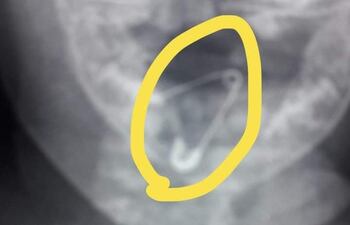

CORONEL OVIEDO. En un trabajo heroico de la pediatra Yéssica Vargas, apoyada por personal de blanco de Hospital Regional de esta ciudad, logró extraer con éxito un prendedor abierto de la garganta de una beba de 8 meses de vida, quien tragó accidentalmente el objeto. Pese a no tener equipos necesarios se ingeniaron para salvar la vida de la criatura.